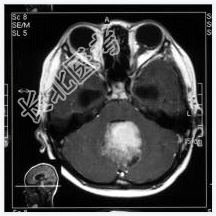

- [材料题] 患者,男性,10岁,因头晕、头疼伴呕吐1月,加重2天入院。做头颅MRI检查。

- 简答题1、诊断及依据是什么?

- 简答题2、鉴别诊断有哪些?